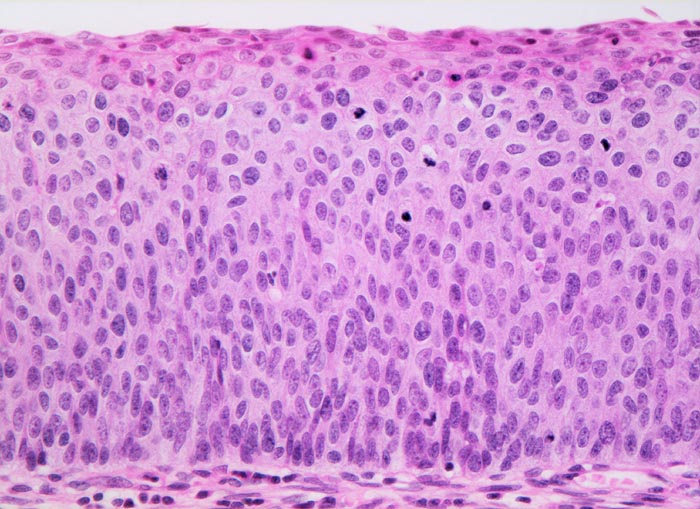

Carcinoma in situ (CIN III) des Plattenepithels

Plattenepithel mit fehlender Ausreifung (wenig Zytoplasma, grosse Kerne) der dichtstehenden Zellen in der gesamten Epithelbreite. Mitosen lassen sich in diesem schwer dysplastischen Epithel bis in das obere Epitheldrittel nachweisen. An der Epitheloberfläche finden sich einzelne parakeratotische Zellen mit kleinen kondensierten pyknotischen Kernen und dunkelrotem dichtem Zytoplasma.

Das Carcinoma in situ wird der schweren Dysplasie (CIN III) gleichgesetzt. Beim Carcinoma in situ lassen sich die dysplastischen Veränderungen und Mitosen in der gesamten Epithelbreite nachweisen.